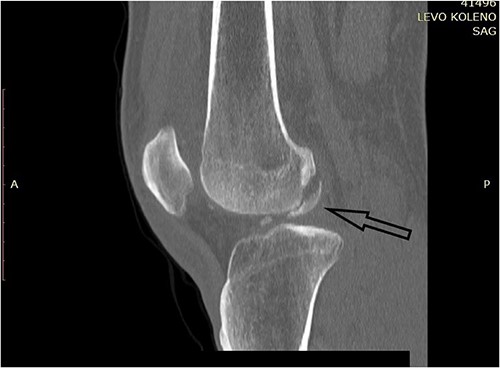

One month after index surgery, the patient was readmitted for the second intervention. In spinal anesthesia, the left knee was positioned for routine arthroscopy. During the procedure, it was concluded that the achievement of proper anatomical fragment repositioning and fixation is unobtainable. Therefore, conversion to arthrotomy followed via the lateral parapatellar approach. Fragments were fixed with two titanium headless compression screws (3.5 mm) (Fig. 4). The second postoperative period was uneventful. Early range of motion exercises started on postoperative Day 2. The patient was discharged on postoperative Day 4. The rehabilitation period lasted 4 weeks. Weight-bearing was allowed at Week 8 after surgery.

Postoperative plain X-ray of the left knee. (A) Anteroposterior view. (B) Lateral view.